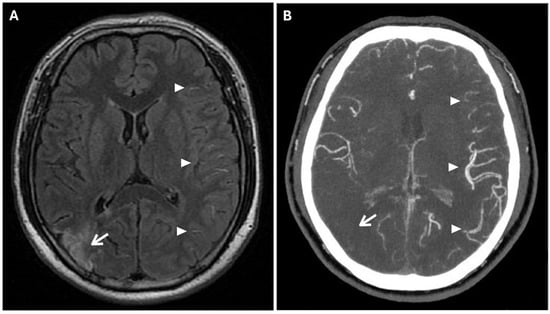

Prominent leptomeningeal collaterals with slow flow, resulting in high signal intensity on FLAIR sequences, were detected in the subarachnoid spaces of the left hemisphere (“ivy sign”) (Figure 4).

Figure 4. The Ivy sign in the left-brain hemisphere. (A) Axial 2D FLAIR sequence shows linear hyperintensity along the cortical sulci of the left hemisphere (white arrowheads); note a subacute ischemic lesion in the right parietal lobe (white arrow). (B) CTA Maximal Intensity Projection (MIP) shows prominent leptomeningeal collaterals in the left hemisphere, with abnormal enhancement of blood vessels, “ivy-like” (white arrowheads); the absence of opacification of distal branches of the right MCA (white arrow) was consistent with recent ischemic stroke in the right parietal lobe vascular territory.

The “ivy” sign is an indicator of slow or retrograde flow in engorged pial vessels, via leptomeningeal collaterals, and is characterized by linear hyperintensity on FLAIR sequences in cerebral sulci of the affected brain region, as in the case we report. The ivy sign is also detected on contrast-enhanced T1-weighted sequences, and it may be less pronounced on 3D FLAIR compared to 2D FLAIR sequences, probably because of the differential impact of flow velocity in the 2D versus 3D FLAIR imaging; it has also been hypothesized that the uniform suppression of the cerebrospinal fluid signal inherent to 3D FLAIR may obscure both the abnormal thickening and/or signal intensity of the leptomeninges, as well as pathological signal alterations within the CSF itself [18,19]. In the case we report, this sign was more evident in the brain hemisphere opposite to the ischemic lesion. This apparent paradox could be explained by the rapid onset of arterial occlusion in the right middle cerebral artery that did not allow the development of compensatory collaterals [20]. The ivy sign has been associated with cerebrovascular reactivity and decreased vascular reserve, and, following revascularization surgery, it can improve or worsen temporarily due to hyperperfusion [14]. Moreover, an elevated Suzuki stage (≥3), CBF reduction, and high risk of severe ischemic events, correlate independently with the ivy sign [21].